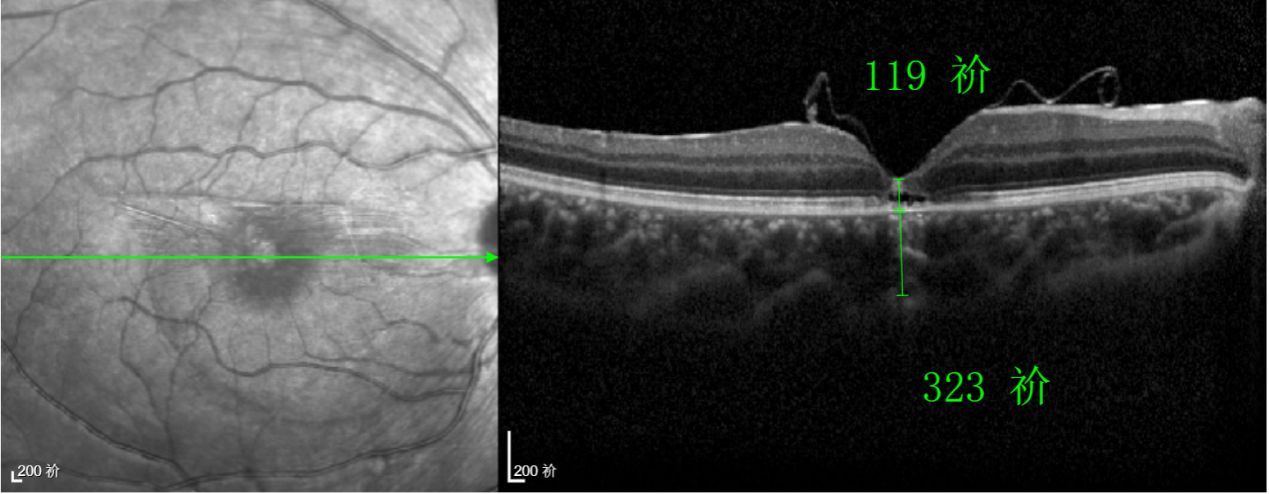

王曉波主任表示:該術(shù)式無需依賴硅油或氣體去頂壓裂孔促進(jìn)愈合,術(shù)后也就無需再保持俯臥體位,這不僅極大提升了患者的舒適度,更顯著提高了治療依從性。對(duì)于活潑好動(dòng)的兒童、難以長時(shí)間保持特殊體位的老年人,以及因其他健康問題無法耐受俯臥的患者而言,這項(xiàng)技術(shù)無疑帶來了巨大的便利和改善。

除此之外,利用自體組織覆蓋為黃斑裂孔提供了理想的愈合環(huán)境,裂孔閉合速度顯著快于傳統(tǒng)方法。誠誠接受手術(shù)24小時(shí)后,檢查可見內(nèi)界膜瓣位置良好;術(shù)后1個(gè)月,黃斑裂孔已經(jīng)閉合,視力恢復(fù)到0.5;術(shù)后兩個(gè)月,視力進(jìn)一步提升到0.7。

“書本的文字都變直了,黑板上的字也更清晰了!”

術(shù)后3個(gè)月復(fù)查時(shí),小男孩的眼睛閃耀著自信的光芒。